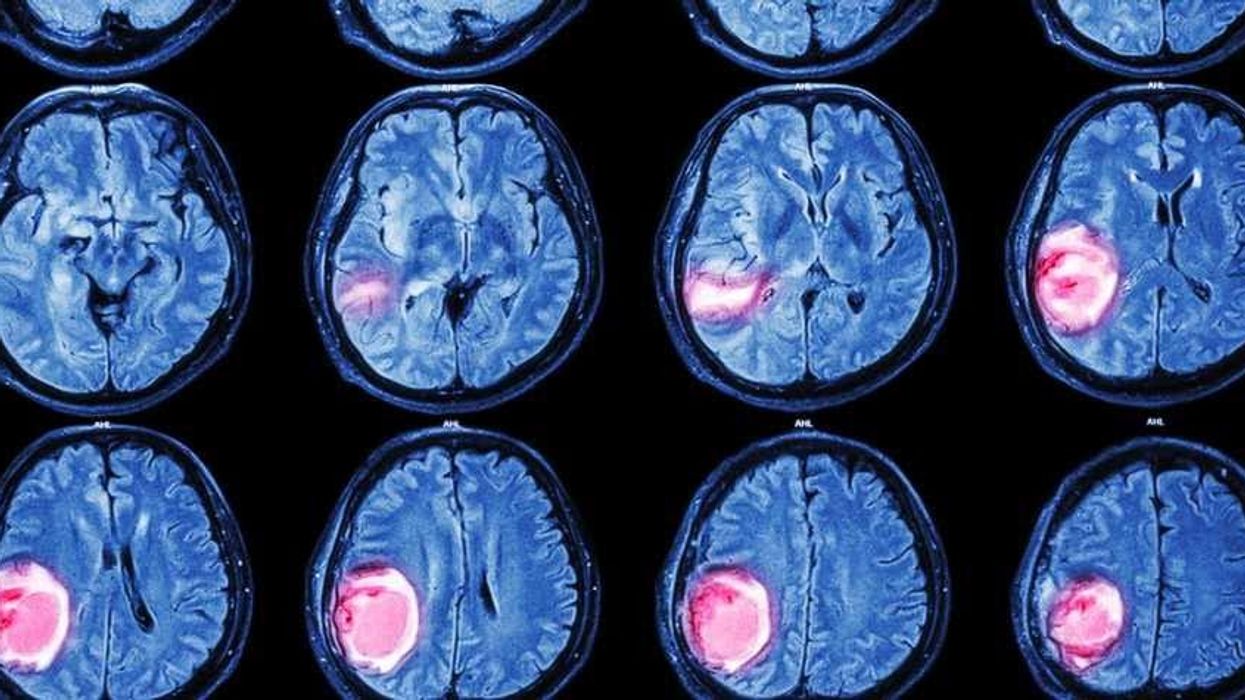

5 gjëra që duhet dini për Tumorin Më Të Shpeshtë Të Trurit

Diagnoza e tumorit të trurit mund të tingëllojë si situatë vdekjeprurëse. Por, megjithëse simptomat e shumicës prej tumorëve të trurit janë të njëjta, jo të gjithë tumorët janë malinjë.

Në fakt, meningjioma është lloji më i shpeshtë i tumorit, duke i përfshirë 30% të tyre.